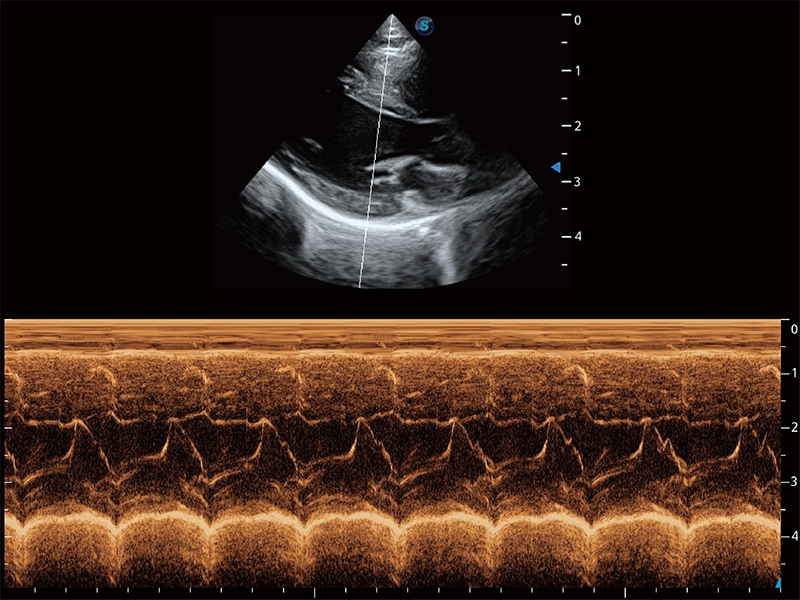

• AMM 解剖M型

通过360度任意调节3条M型取样线,在同一心动周期上观察心脏不同位置的运动曲线,得到准确的心功能测量数据,有效评估心肌运动及左心室功能。

优异的基础图像

ProPet 80 全新的动物超声智能软件和丰富的探头群,为动物医生提供了高清晰度和精细分辨率的图像,无论在宠物、马科、畜牧还是实验室动物等应用中都可以轻松应对,为您的日常工作带来满意的体验。

(猫)二尖瓣M型